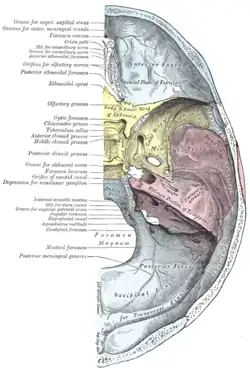

Base of the skull, inner surface | |

Base of the skull. Upper surface

Base of the skull. Upper surface Base of skull